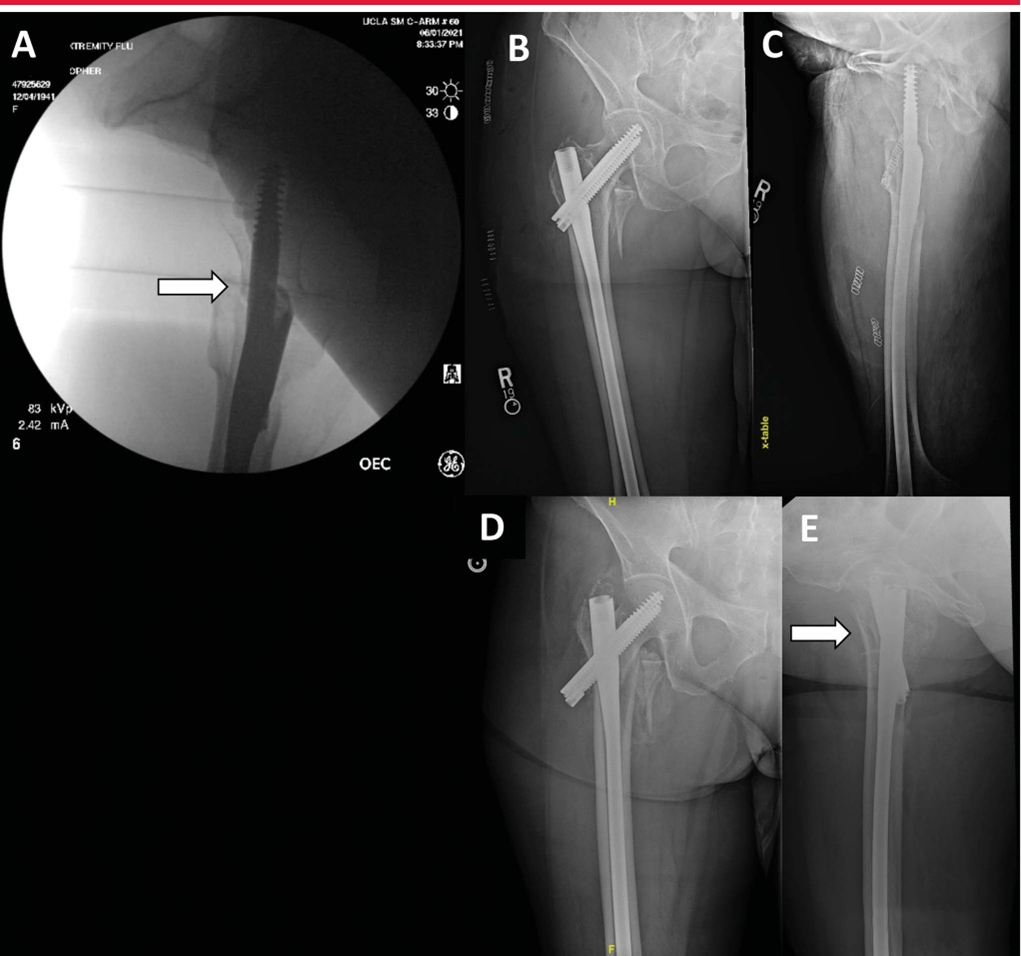

Вид с боковой редукцией показывает переднемедиальную кортикальную поддержку (стрелка). B: Послеоперационное AP-изображение, показывающее выравнивание кортикального слоя. C: Послеоперационное боковое изображение демонстрирует деформацию переднемедиальной кортикальной опоры. D-E, AP и боковые проекции показывают значительный коллапс (стрелка) через 6 недель после операции.